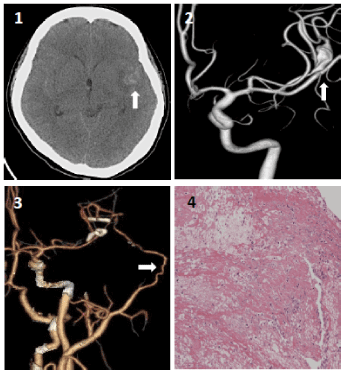

A 33-year-old female was found unconsciousness and sent to our hospital. Initial computed tomography CT) scan revealed diffuse SAH (Figure 1A). Further angiography demonstrated a 1.2 cm fusiform aneurysm with irregularity of distal left MCA (Figure 1B). Tracing the past history of this patient, there was no evident risk factors associated with such an aneurysm formation. Between clipping reconstruction and trapping with cerebral revascularization, we chose the latter due to complex aneurysm morphology and unclear etiology of aneurysm formation. We performed a standard pterional approach, a fusiform aneurysm located at upper trunk of MCA was found. As torturousity and irregularity of the aneurysm made direct aneurysm clipping difficult and unsecure, a left superficial temporal artery to MCA bypass and trapping of lesioned parent artery were done to secure the ruptured fusiform aneurysm and preserve distal left MCA perfusion. The patient got uneventful recovery after surgical procedures. Postoperative CT angiography revealed patent anastomosis with preserved perfusion in the MCA territory (Figure 1C). The aneurysm wall was taken for pathological examination.

Figure 1. (1A). Brain computed tomography scan showed diffuse SAH dominantly over left sylvian fissure (white arrow). (1B). Reconstruction of left internal carotid artery angiography showed fusiform aneurysm at the left distal middle carotid artery (white arrow). (1C). Reconstruction of computed tomography angiography shows patent bypass artery (white arrow) from superficial temporal artery to distal middle carotid artery. Two aneurysm clips were applied for aneurysm trapping. (1D). Pathological study for the segment of aneurysm wall demonstrates fibrinous exudate and necrotic debris with additional lymphocytes, histiocytes, a few plasma cells, and rare polymorphonuclear cells (hematoxylineosin and Luxol fast blue, 20X)

Further laboratory test indicated anti-nuclear antibody was1:1280X with a typical speckled pattern. Rheumatic factors Anti-Ro and Anti-La moderately elevated to149.61 IU/ml and 386.84 IU/ml respectively. She developed malar rash outbreak 2 weeks after the surgery. Skin biopsy revealed picture of interface dermatitis with vacuolar degeneration of the basal layer of the epidermis. Also, it shows moderate C3 antibody marker granular deposition in the dermoepidermal junction and linear deposition in the basement membrane of hair follicles and sweat glands. She was later diagnosed with SLE. On pathology, the aneurysm wall revealed granulation with fibrinous exudate and necrotic inflammation debris (Figure 1D), which are also compatible with pathological change in SLE.